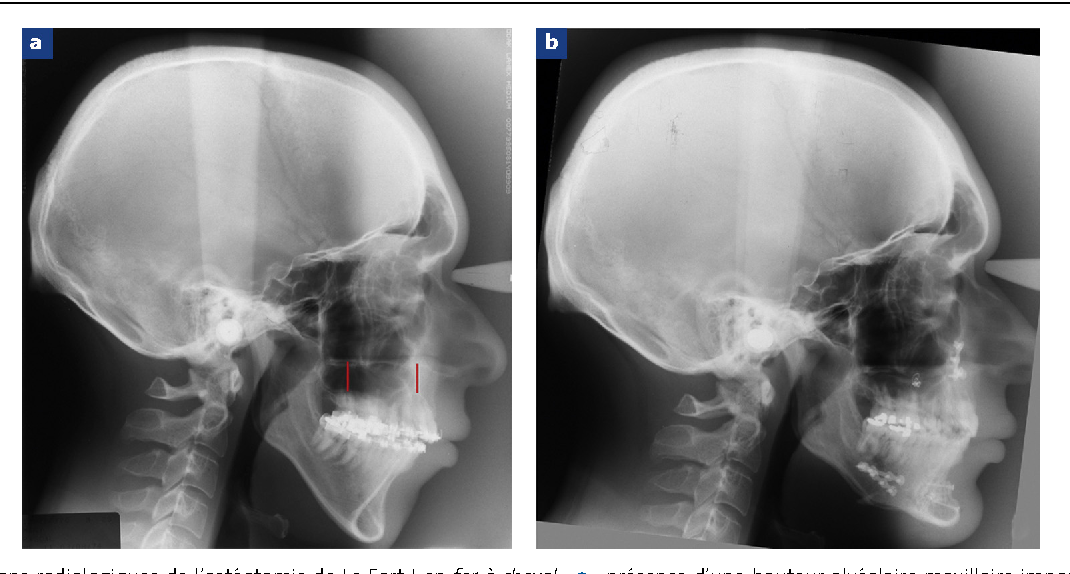

@thecel I don't know if you already know this. There's some hope for the long midfaces of downgrown jaws.

This guy's before-and-after is dotted around the place. He underwent a surgery called Horseshoe Osteotomy. It's like maxillary impaction, but a slice of the maxilla precisely parallel to the occlusal plane is deducted. Usually I think it's a sector with the angle of CCW movement, that's how downswung patients are fixed. However, if your occlusal plane is right, it needs to be zero; the point of Horseshoe Osteotomy.

5601677_1764482344566.png

Now it's really quite remarkable and hopefuel because in the before he is downgrown, the problematic type of mismatch of dental planes. In the after, the surgeon snapped his MPA into two, and bent it into shape with staples. The midface is compacted because of the strip of bone that was exhumed. In the after his midface ratio is better, his MPA is better, and he gained a chin. Amazing result that is relevant to this thread and how to combat rare causes of long midface; not all long midfaces are caused by mouth breathing, and its your thread, and radiographs like in the before-and-after that helps us recognise and diagnose that.

Edit: whoops. Forgot to upload this annotated closeup of the radiograph. You can see more clearly what the surgeon set out to remove. Inspiring stuff. Genuine hopefuel.

2 Figure1 1